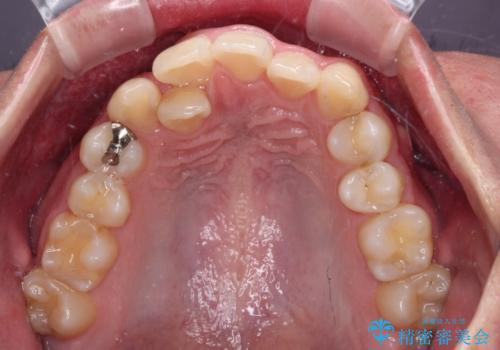

- 今回ご紹介するのは、

「全体的なデコボコ(叢生)」「上下の正中のずれ」 を主訴として来院された20代男性の患者様の症例です。

叢生が強く、歯が並ぶスペースが不足していたため、

上下左右の第一小臼歯を抜歯して、矯正治療のための適切なスペースを確保する計画としました。

上顎左側第一大臼歯に齲蝕が認められたため、矯正治療終了後に 精度の高いセラミックインレー にて修復治療を行いました。